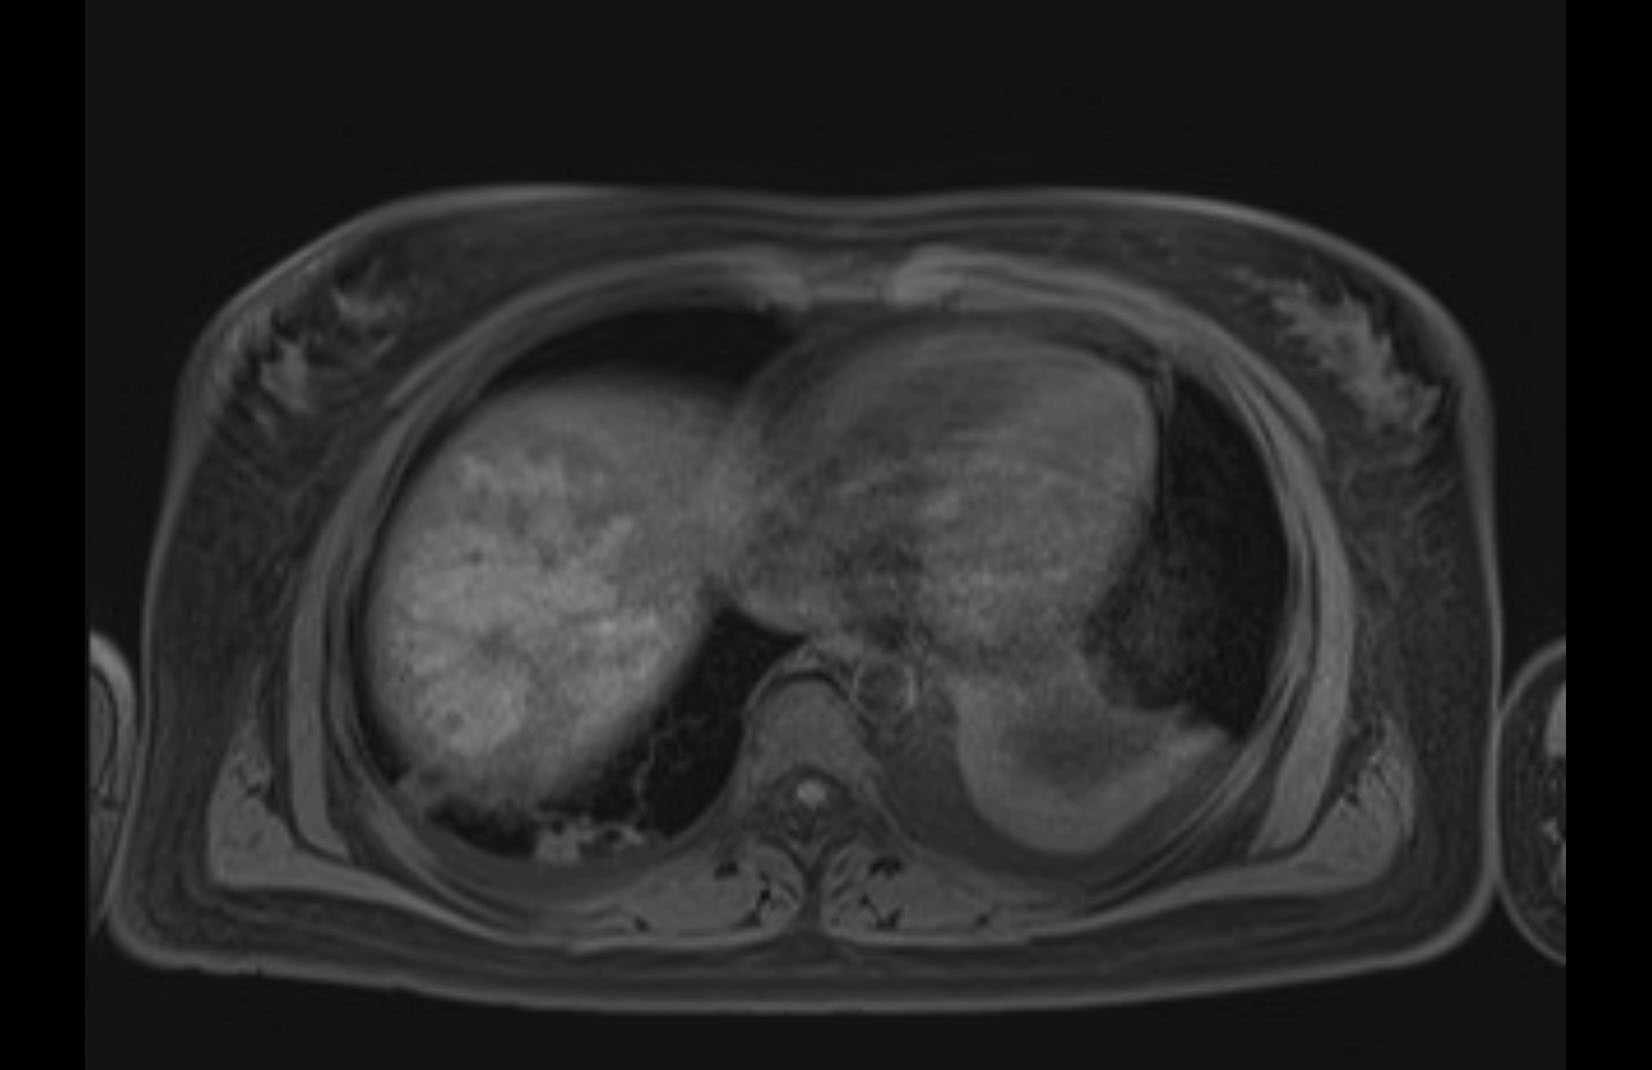

MRI T1